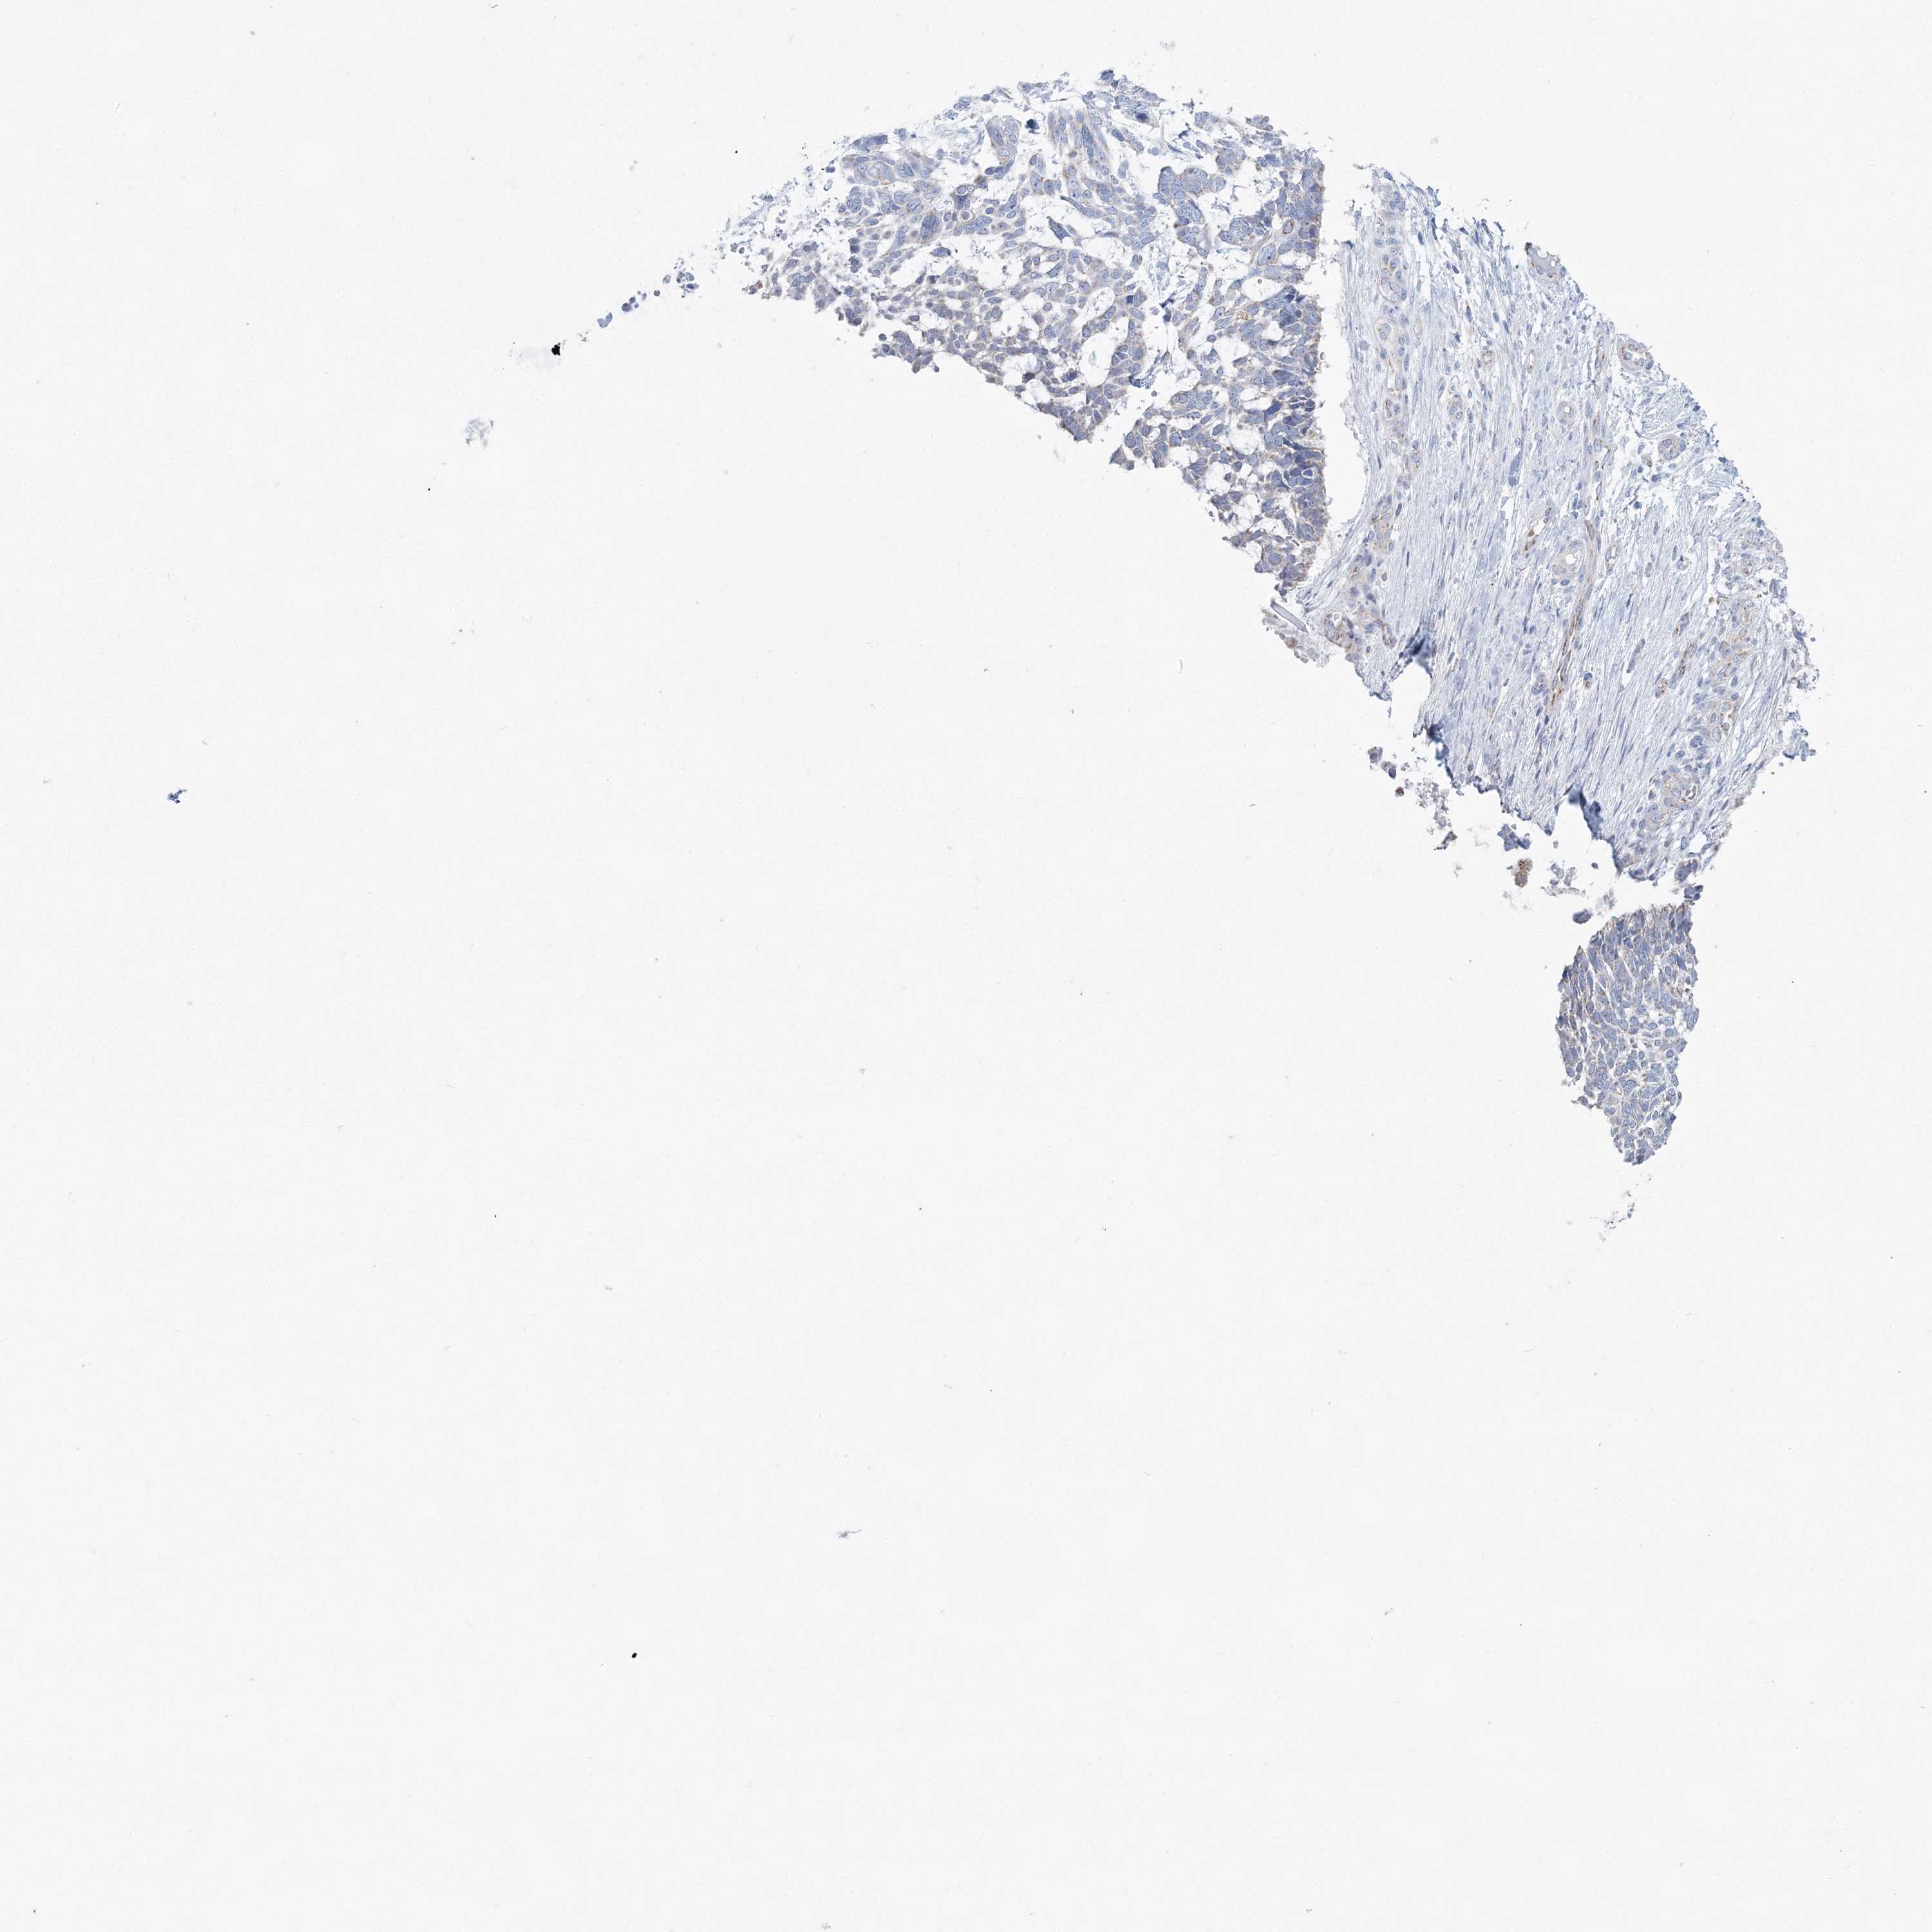

CANCER SKIN CANCER Show tissue menu

SKIN CANCER - Protein expressioni

A mouse-over function shows sample information and annotation data. Click on an image to view it in a full screen mode. Samples can be filtered based on level of antibody staining by selecting one or several of the following categories: high, medium, low and not detected. The assay and annotation is described here.

Each image is clickable and will lead to virtual microscopy that enables deeper exploration of all samples and also displays staining intensity scores, fraction scores and subcellular localization as well as patient and tissue information for each sample.

Antibody HPA036540

Antibody HPA036541

Basal cell carcinoma

Squamous cell carcinoma, NOS

Squamous cell carcinoma, metastatic, NOS